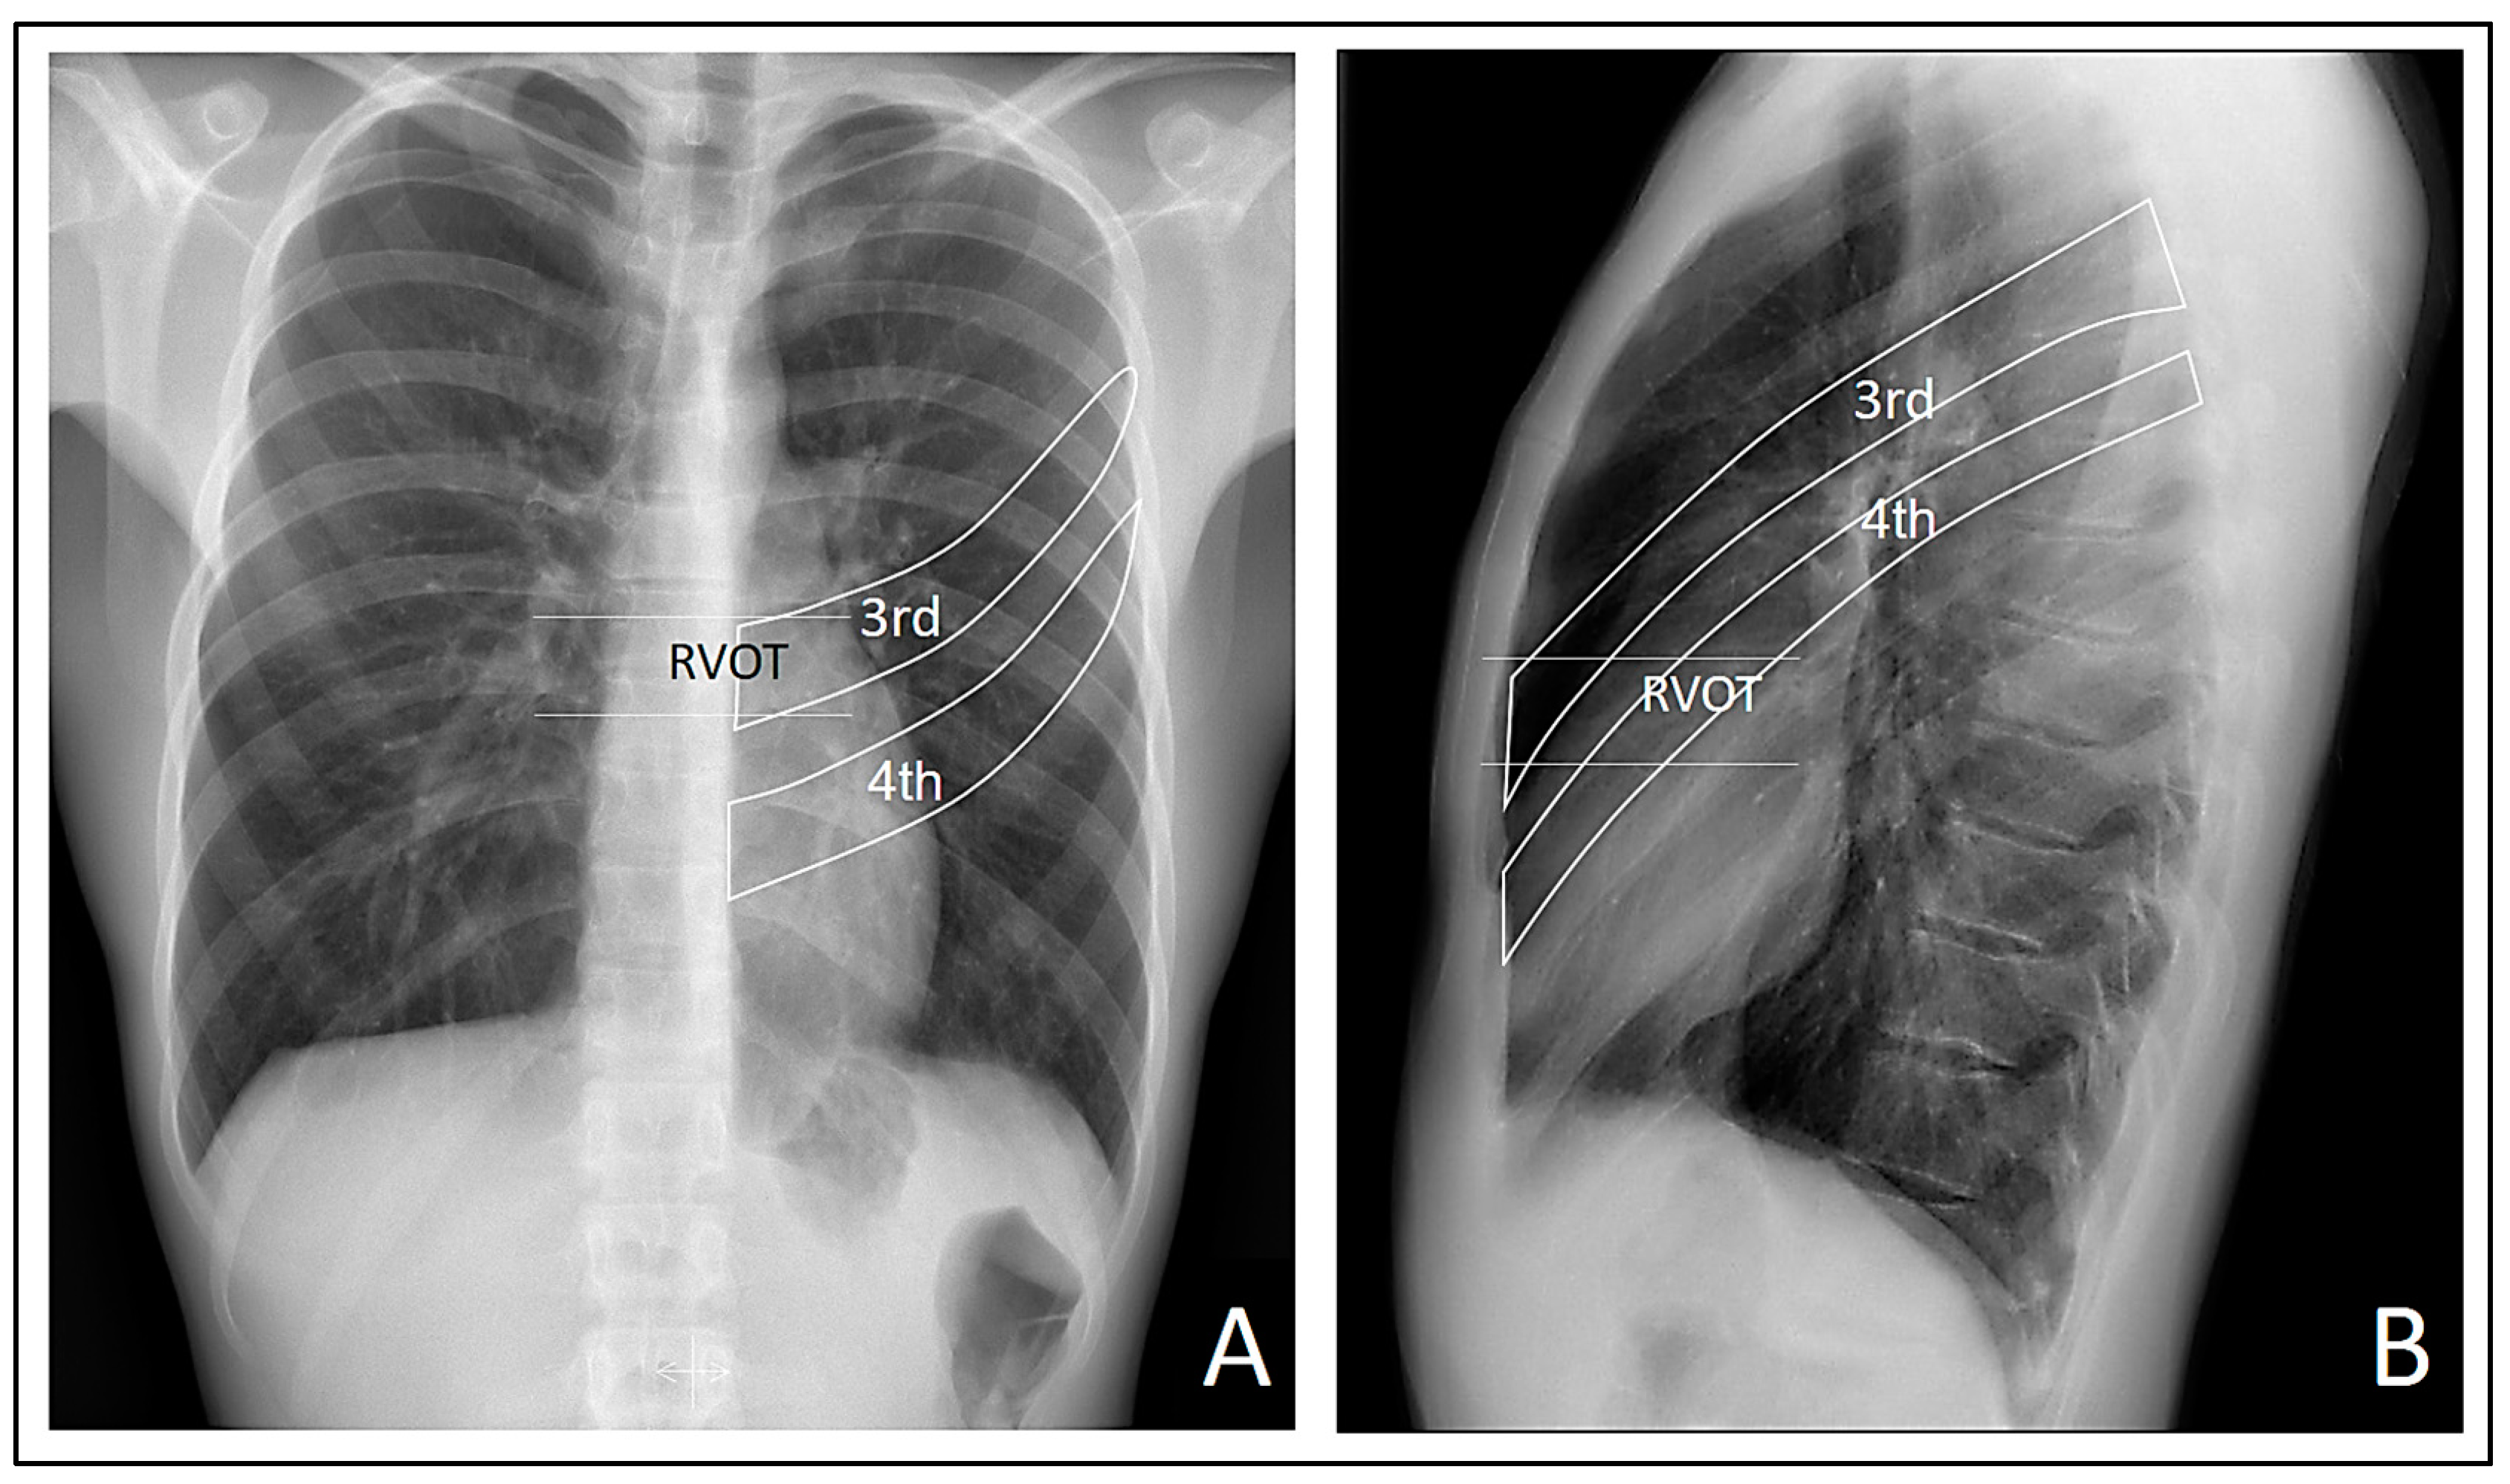

All the patient’s vital signs were within normal ranges. A posteroanterior and lateral chest X-ray, along with an electrocardiogram, were ordered. Although the pulmonary auscultation did not yield typical findings suggestive of any pulmonary parenchymal or pleural cavity pathology, the posteroanterior chest X-ray revealed a small pneumothorax at the right apex (Figure 1A). Consequently, the patient was referred to the Hospital Urgency Department, and an urgent consultation with Thoracic Surgery was requested.

In addition, the lateral chest X-ray showed no radiological signs of cardiac compression due to the sternocostal structural anomaly (Figure 1B).

The observed patterns were most clearly visualized in the right precordial leads, specifically in V1 and V2. This finding suggests a possible direct involvement of the electrical signals captured by the electrodes closest to the right ventricle, influenced or not by the thoracic deformity in the form of pectus carinatum. It is not possible to ascertain or rule out that the thoracic deformity leads to the appearance of Brugada patterns when focusing electrode measurement in the region of the RVOT. However, when we moved the electrodes up and down from the third and fourth intercostal spaces, the characteristic morphology of the Brugada patterns was lost, suggesting a possible involvement of the RVOT in the genesis of these patterns. This is visually confirmed in the lateral radiograph where it can be observed that indeed the third and fourth intercostal spaces are closer to the likely radiographic location of the RVOT (Figure 7).

Contrary to the assertions made in scientific literature [1,2,6], the proposal of a cardiac compressive explanation at the right ventricular level to elucidate the Brugada patterns observed in our patient lacks logical coherence. This assertion is supported by radiological studies represented in Figure 1 and Figure 6, which revealed an absence of evident compression attributable to the thoracic disposition of pectus carinatum.

Figure 1. A: Posteroanterior chest X-ray showing the small pneumothorax at the right apex (the white arrow indicates the pleural edge). B: Lateral chest X-ray, where it is evident that the patient’s sternocostal disposition does not cause cardiac compression.

Figure 7. We take Figure 2 again and highlight the probable location of the RVOT and the third and fourth intercostal spaces. Note that the RVOT is positioned behind the third intercostal space in our patient.